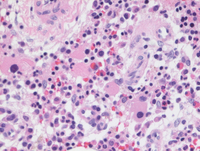

Bone core biopsy

Bone core biopsy shows a slightly hypercellular marrow with very occasional atypical megakaryocytes. Otherwise, background myeloid maturation is progressive and normal while erythroid precursors are appropriately intermingled. About 2-3% CD34+ blasts were present (not shown).